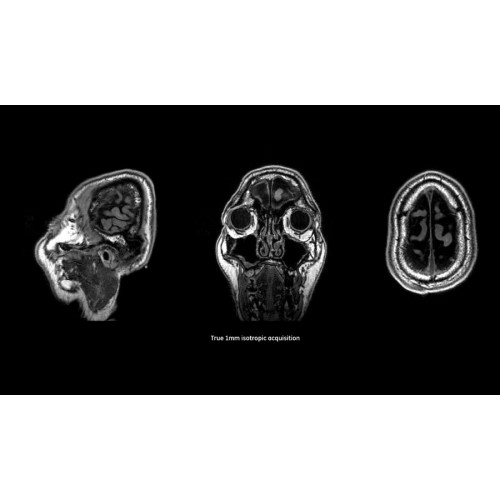

МРТ аппарат GE SIGNA Voyager 1.5T позволяет проводить полный спектр магнитно-резонансных исследований, включая нейровизуализацию, исследования опорно-двигательного аппарата, органов брюшной полости и малого таза, а также специализированные кардиологические программы.

• Неврология и нейрохирургия

МРТ-аппараты, Полуоткрытые аппараты МРТ, МРТ аппараты для животных